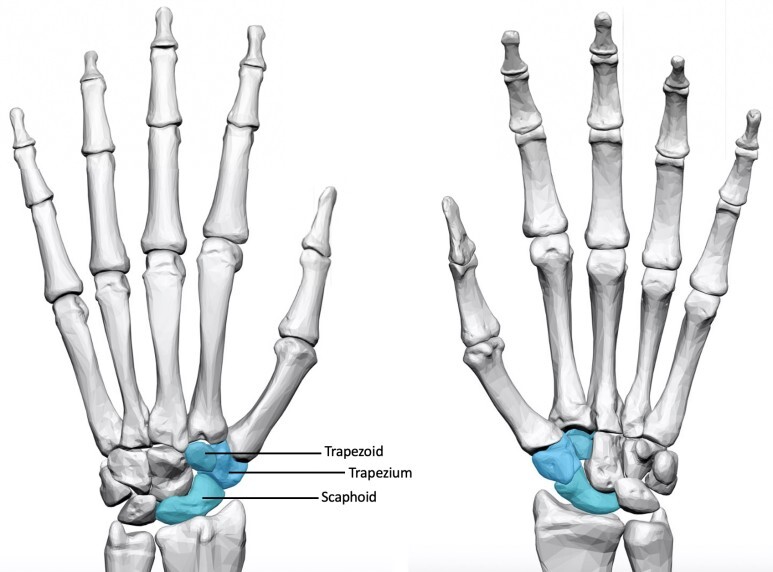

- 손목을 이루는 모든 관절에서 발생할 수 있습니다. 특히 주상골(Scaphoid)와 관련되어서 많이 발생하게 됩니다. 거의 손목의 관절염에서 90%이상이 주상골과 관련되어 있다고는 연구도 있습니다.

- 앞서 말했듯 퇴행은 주상골주변에서 가장 많이 발생합니다.

- 보통 처음에는 요골경상골기(Radial styloid)와 주상골의 닿는 부분에서 관절염이 우선 발생되고 이 후 주변 관절로 침범하게 됩니다.

- 원위열 4개뼈

- 대능형골(Trapezium), 소능형골(Trapezoid), 유두골(Capitate), 유구골(Hamate)